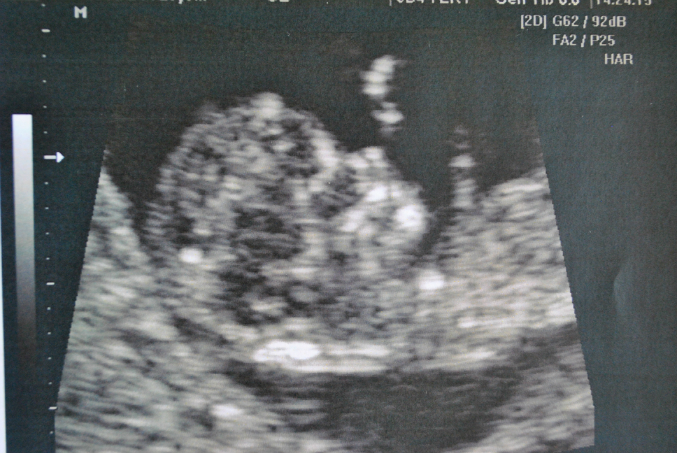

Скрининговое УЗИ 12я неделька)

Анализы, скринингиЯ дождалась нашего узи) Боже, я ничего в жизни прекраснее не видела) Сказали, что скорее всего девочка)) Так же все в норме, все хорошо, по месячным у нас 11 недель и 4 дня, по узи 11 недель и 2 дня) ктр 45,2 мм) Сердечко бьется 158 ударов в минуту) Про все органы написано N, а вот четвертый желудочек - 1,8 мм, это что вне нормы???? Под катом фоточки моей малышки (надеюсь она не превратиться в мальчика)))) Как же это все волнительно))))